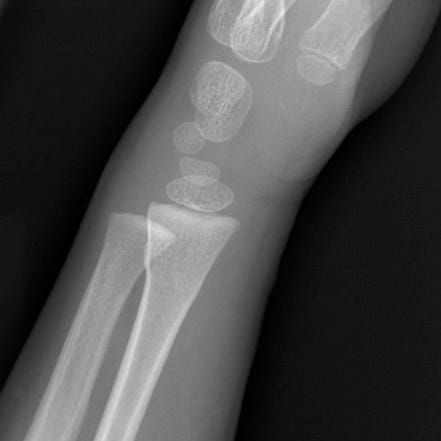

Forearm buckle or torus fractures are common in children and are usually due to falling on an outstretched arm. Force transmitted along the extremity axis results in compression of trabecular bone and bulging of the adjacent cortex without a distinct fracture line. Subtle cortical buckling or angulation may be the only radiographic finding. Common symptoms are pain, tenderness, swelling, and inability to rotate the forearm.

Buckle (torus) fracture. Mild cortical buckling along the dorso-radial aspect of the radial metaphysis. No displacement or angulation.

While radiographs are typically obtained, ultrasound can also be used for diagnosis. Treatment consists of immobilization and prompt orthopedic follow-up. These fractures have a good prognosis, and com- plications are rare.